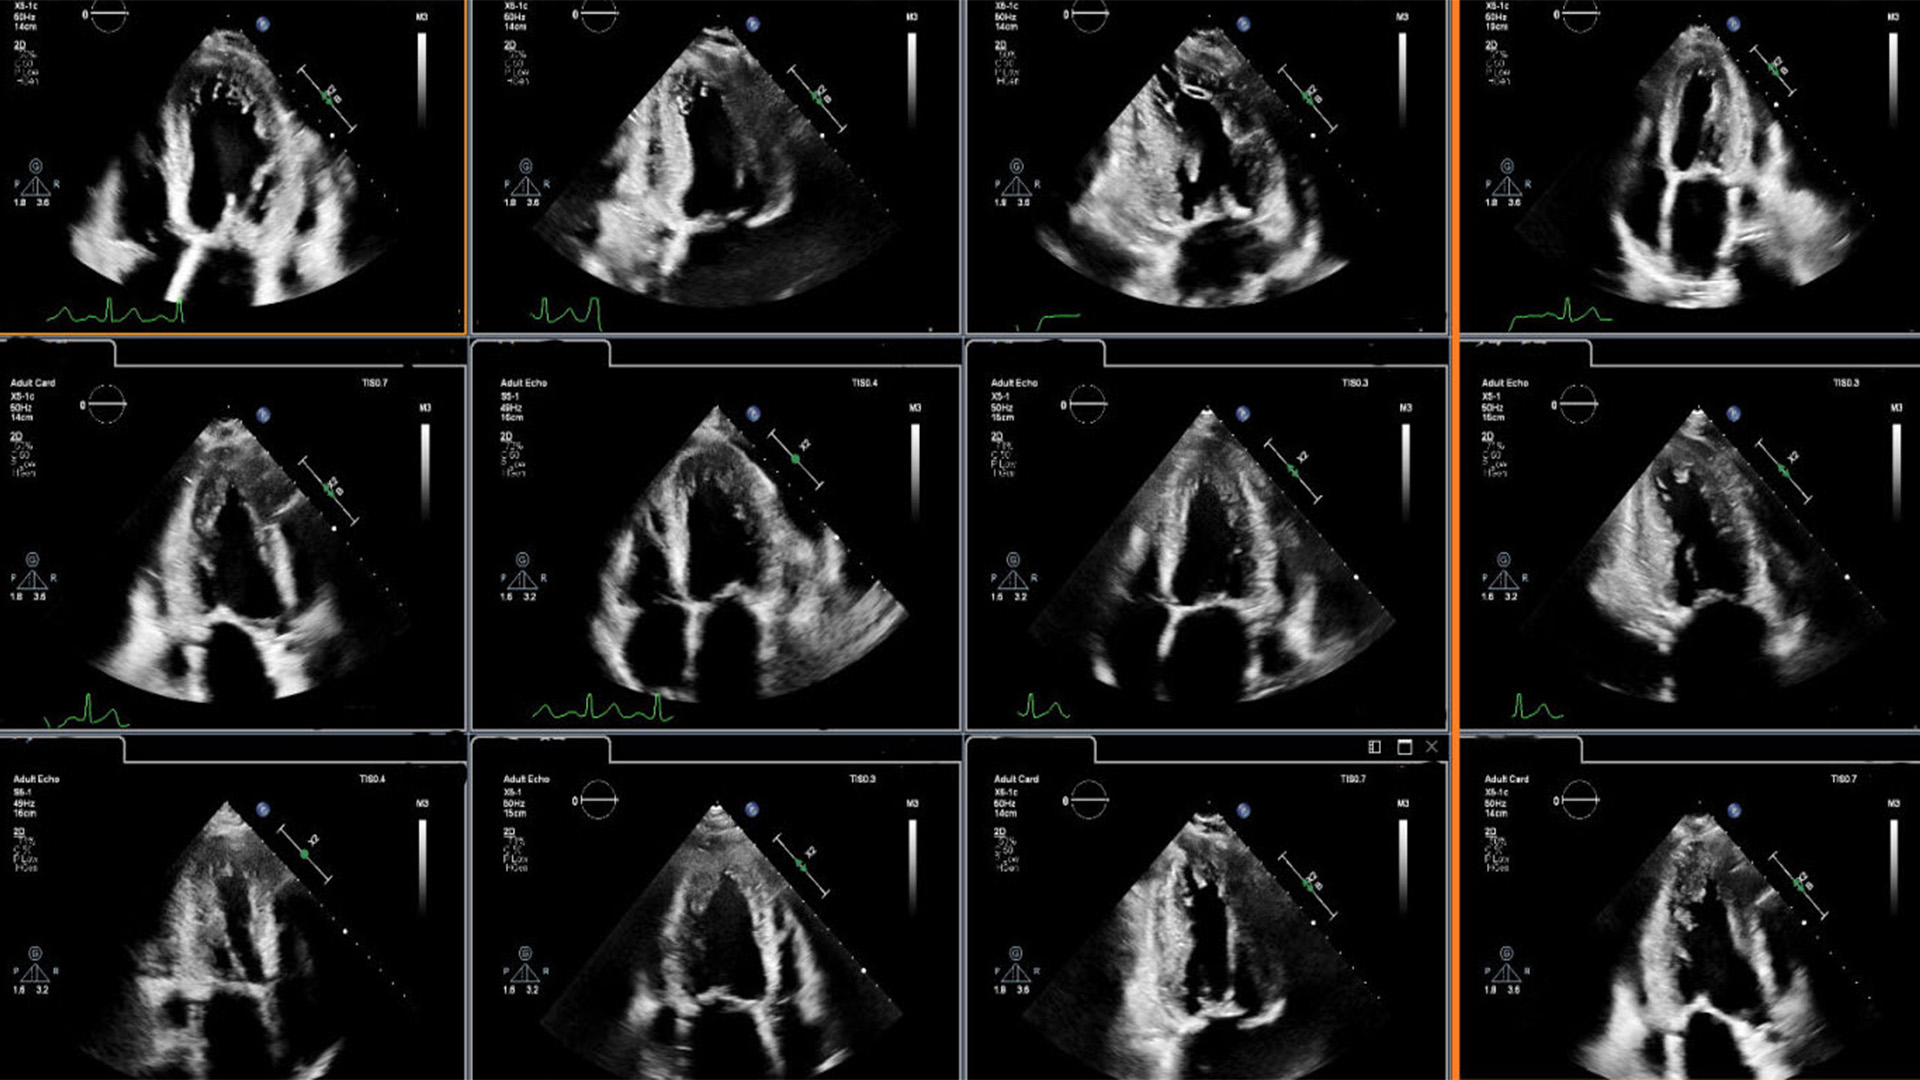

Dr. Lang will join other clinicians to share the results of a new scientific abstract being presented at the American Society of Echocardiography (ASE2024) annual meeting (June 14 – 16, Portland, US), demonstrating how first-of-kind AI algorithms co-developed with Philips provide highly accurate detection of regional wall motion abnormalities (RWMA) on echocardiography. RWMAs can be an independent indicator of adverse cardiovascular events and death in patients with cardiovascular diseases like myocardial infarction (MI) and congenital heart disease. Automated machine learning-based assessment of RWMA has the potential to improve the efficiency of all readers. “An advantage of AI methods over conventional visual analysis is that it can be performed in seconds, providing rapid and accurate information to help augment expert reads by quickly highlighting areas of concern for RWMA, improving the ease and efficiency of interpretation,” Lang added.

- Clinical image showing how integrating AI into cardiac ultrasound provides automated segmental wall motion scoring

- Clinical image showing cardiac ultrasound display for image analysis enhanced through integration of AI.